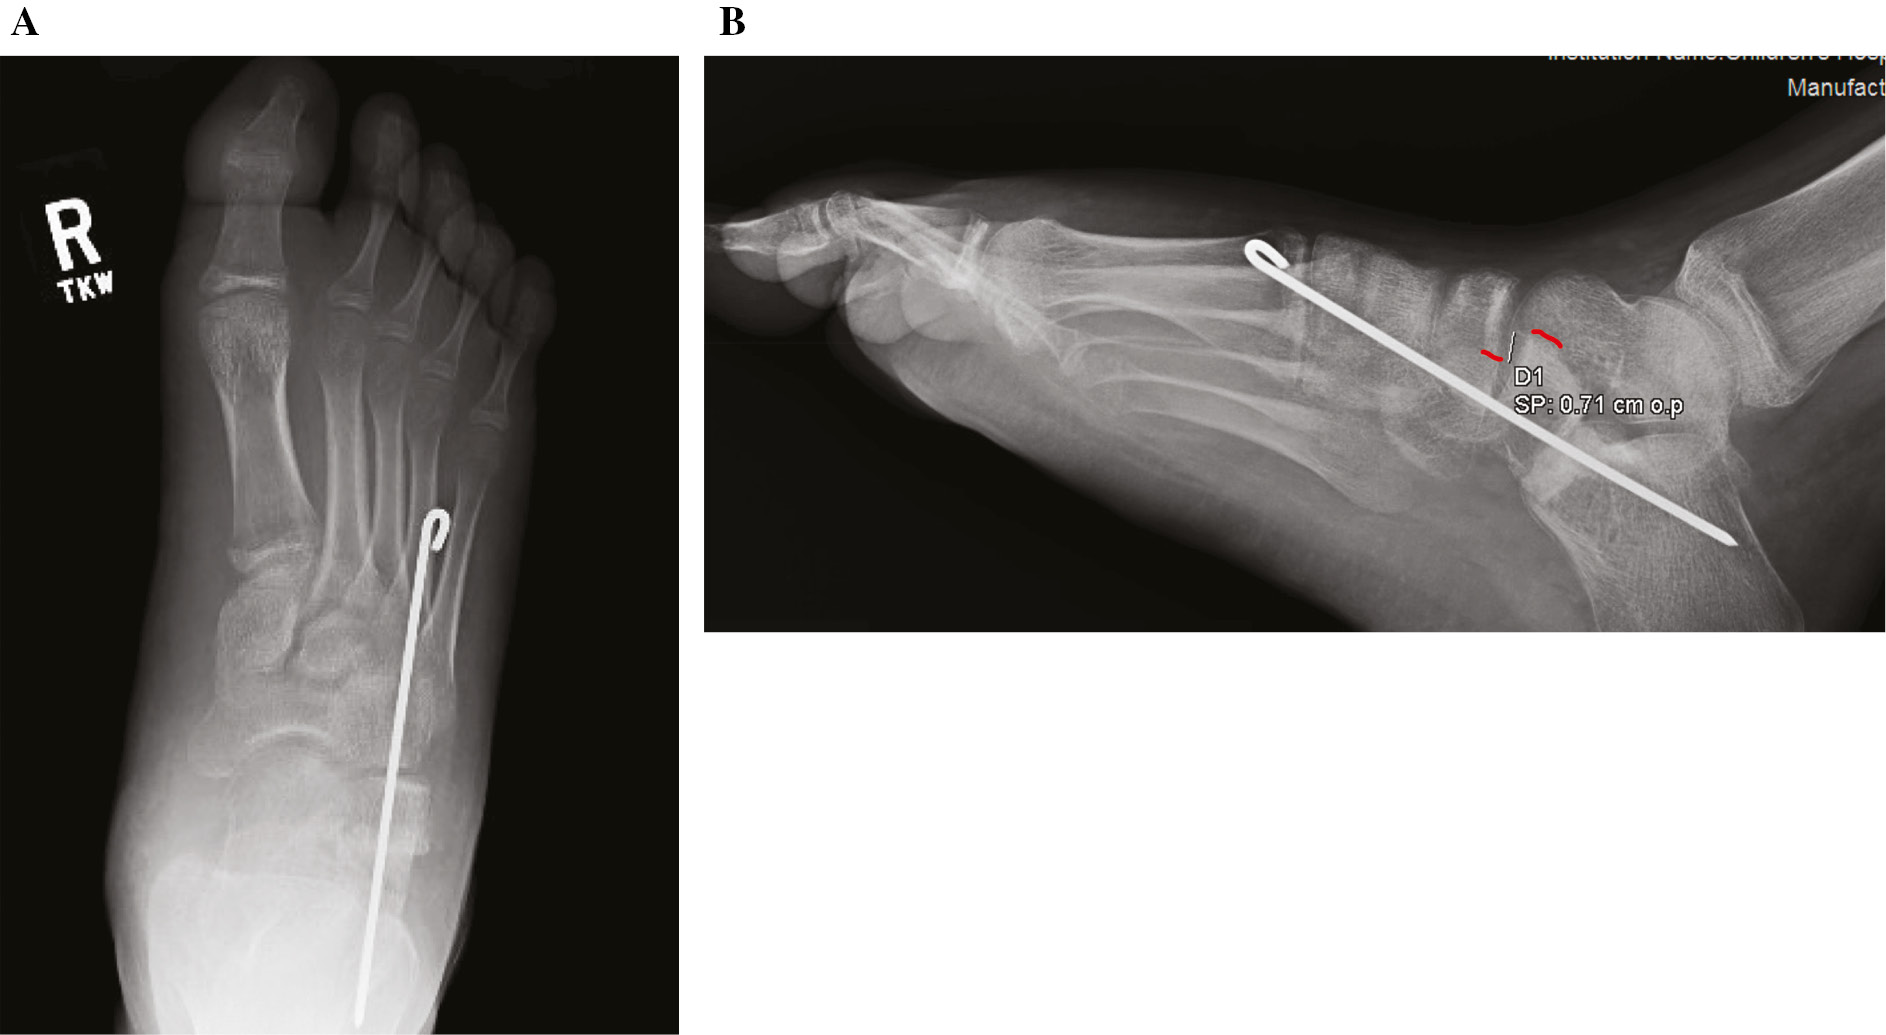

In the typical patient undergoing CLO, there is a difference in the radiographic appearance of the CC joint on the lateral view when comparing the preoperative standing films with intraoperative films with the forefoot plantar flexed. Figure 5 demonstrates the difference in radiographic appearance of the CC joint with dorsiflexion versus plantarflexion force. How much of this radiographic appearance is due to rotation versus plantar translation of the cuboid is debatable, and the placement of two pins has been suggested to mitigate rotatory subluxation of the joint.6

Figure 5. Lateral C-arm radiographs of the foot in a young adult with hypermobile flatfeet (A) with dorsiflexion force and (B) with plantarflexion force. Note the difference in the relative positions of the dorsal cortex of the calcaneus and cuboid (red lines).